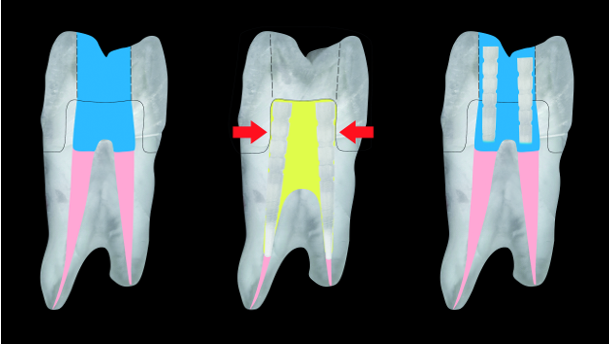

Traditionally, minimally accessed endodontically treated teeth that are not extensively compromised by caries or fracture, have been restored solely with a composite core, without the placement of a post. This decision must be based on the amount of tooth structure left, and if a full coverage restoration is to be placed now or in the future. The width and height of the ferrule remaining is critical to restorative success (Figs. 1a & b), [3-6] as well as the number of tooth walls left, post preparation, which significantly affects the long-term restorative outcome (Fig. 2). [6-8]

So where does this lead us in a suggested modification of our restorative technique for placing a core in an endodontically treated tooth? Currently, when there are enough walls and tooth structure left, many clinicians insert a bulk fill, dual-cure composite resin into the endodontic access opening (the same material as that used for cementing the fibre post) and then cure it all at once with an LED curing light. As already mentioned, this bulk fill not only creates a challenge for proper depth of cure and maximum physical properties on polymerisation, which will be addressed later in this article, but the large volume/amount of composite inserted, negatively affects the integrity of adhesion and increases microleakage. The typical access opening, which is essentially a very deep Class I cavity preparation, not only requires a large amount of composite, but as well, places the composite in the highest C-factor cavity preparation configuration of five. Only when utilizing a composite deep in the prepared root canal, has the C-Factor claimed to be higher at 200 to infinity. [39]

The suggested solution to the high polymerization and contraction stress caused by bulk filling the access opening is to reduce the mass or bulk of composite by placing multiple Fiber Post Segments into the composite mass, before curing with the LED light. It has been conclusively shown that even when the C-Factor is at 200 or more in a prepared root canal, minimizing the thickness of the composite (the mass), results in less contraction stress (S-Factor) which increases the patency of the bond to the root canal walls decreasing microleakage. [40-43] Of course, the placement of inserts into composite is not a new idea. Glass ceramic inserts and beta quartz have been used to decrease composite volumeand later silica glass and ceramics were introduced as a method for post-composite insertion bulk reduction. [44-46] These techniques demonstrated increased marginal patency and less microleakage, but the inserts were difficult to contour and polish with adhesion between the inserts and the composite being a challenge. [47,48] Composite megafillers were introduced later, as these were essentially the same as the matrix of the bulk filled composite, eliminating the inherent chemical differences between the materials. [49,50] The authors suggest the insertion of multiple high quality, high capacity, light conducting fibre post segments (not all fibre posts conduct light efficiently [51,52]). This is not only to reduce the composite volume, thereby minimizing the potential for microleakage, but is also equally as critical to use the light conductance of the fibre post segments to significantly increase the degree of polymerization of the dual-cure composite resin cements/core materials deep in the access opening, thereby increasing their physical properties. [53]